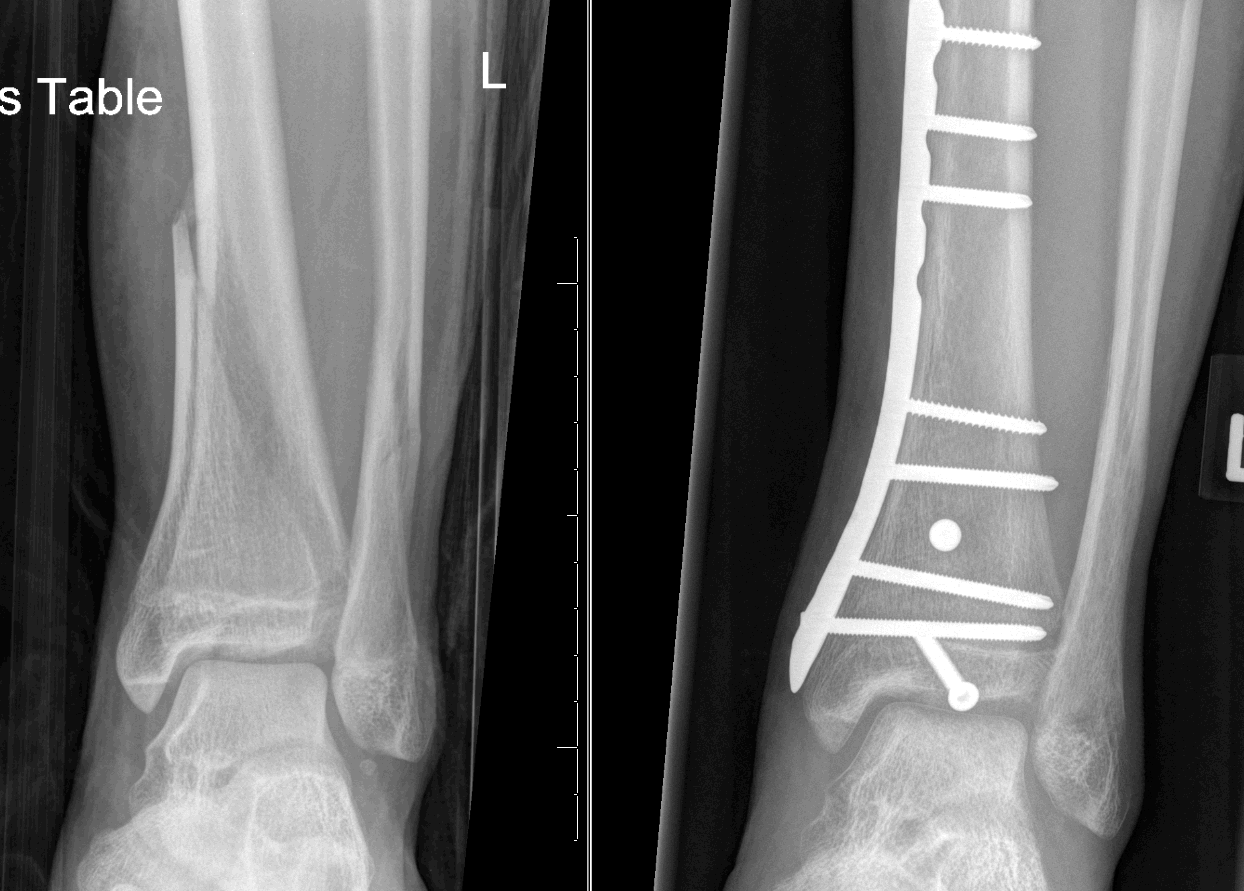

AP radiograph of a medial tibial plateau fracture treated by ORIF with Cpt Code For Tibial Plateau Fracture Orif Orif bicondylar tibial plateau fracture. tibial plateau fractures are periarticular injuries of the proximal tibia frequently associated with soft tissue. the incision should begin distally about 2 cm lateral to the tibial crest, curving over the tubercle of gerdy then. tibial plateau fractures (tpfs) are regarded as challenging fractures to reduce and stabilise, typically requiring. If the. Cpt Code For Tibial Plateau Fracture Orif.